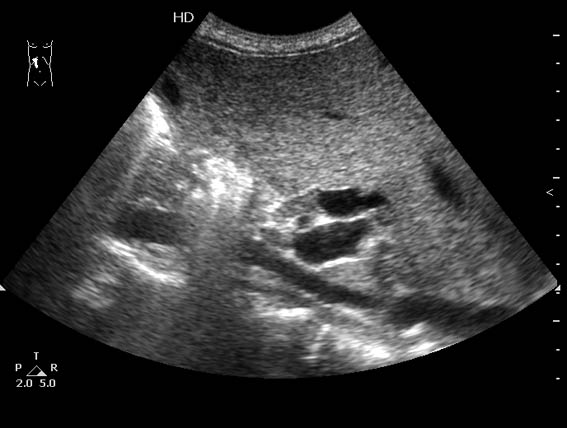

конкремента не вижу. желчный пузырь с утолщенными, слоистыми стенками, как при гепатите А, однако печень обычной эхогенности, да и подобные изменения стенок желчного - происходит в дожелтушный период. При этом расширенные желчные протоки и что-то изоэхогенное(Клацкин?)... я в шоке!

А стрелкой обозначено то самое, что ищем.

судя по снимкам и видео жп не самое главное, впечатления после покадрового просмотра и зума области интереса

клип первый:

образование холедоха?

образование печени - изоэхогенное сдавливающий холедох?

клип второй: стенка холедоха уже не так четко

около ВВ вроде бы л/у небольшой овальный мелькнул

Да, похоже что это опухоль Клацкин - холангиокарциннома зоны слияния правого и левого жёлчных протоков. На втором видео отчетливо видно, что эта зона заполнена изоэхогенным новообразованием.